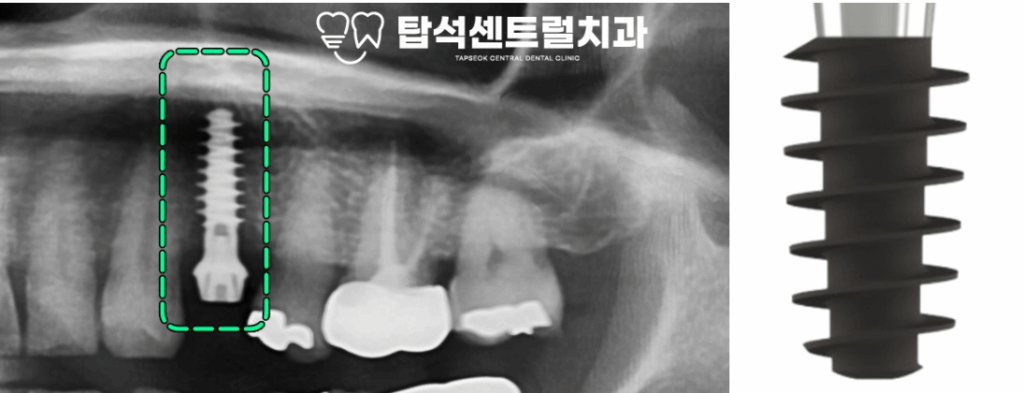

IBS의 또 다른 특징은

픽스처의 구조에 있습니다.

엑스레이 상에서 보았을 때

특수한 나사 구조를 보이고 있어

치조골과 닿는 표면적이 넓고,

나사선 사이 치조골이 거의 훼손되지 않기에

골 흡수가 거의 나타나지 않습니다.

더불어, 안쪽 골막과 분리되지 않아

피질 골이 흡수되지 않는다는

특징을 가지고 있습니다.